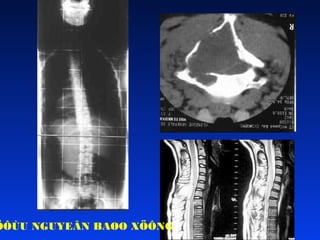

GAÕY C1 – C2

• CT SCAN

• CAÙC LOAÏI GAÕY KHOÂNG VÖÕNG